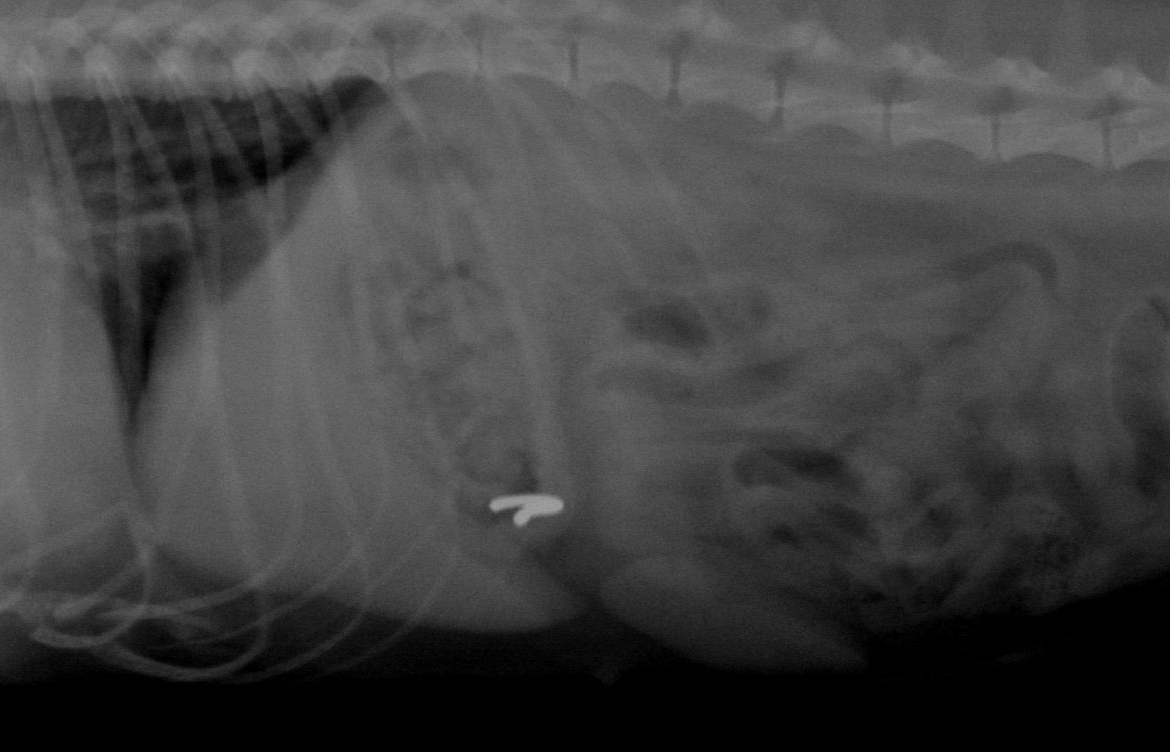

CUERPOS EXTRAÑOS

LOS CUERPOS EXTRAÑOS que llegan al estómago podrán ocasionar la perforación intestinal con el resultante de peritonitis por lo que deben ser extraídos con celeridad.

Los hábitos alimentarios poco discriminatorios de los perros facilitan la presentación de este tipo de patologías. Son muchos los «objetos» que nos hemos encontrado en el aparato digestivo de los perros a lo largo de los años: tetinas, chupetes, piedras, huesos, prendas del hogar, ropa interior, agujas, broches, bolígrafos, juguetes, mecheros, preservativos, pelotas… Lo malo en estos casos, es que los perros que ingieren objetos, suelen hacerlo repetidas veces, por lo que no es raro que tengan que ser operados por obstrucción intestinal varias veces a lo largo de su vida. El vómito (no la regurgitación) es una manifestación común, pero algunos pacientes presentan solo anorexia, mientras que otros son asintomáticos.

El comienzo agudo de vómito en un paciente, de otro modo normal, en especial en un cachorro, sugiere la ingestión de un cuerpo extraño. El objeto puede ser palpable durante la exploración, aunque no siempre es así, o ser reconocido en una radiografía simple. Las placas radiográficas contrastadas, la ecografía y la endoscopia son los medios de diagnóstico más indicados, ya que no todos los cuerpos extraños se dejan ver en una radiografía simple. Además, si el estómago tiene contenido alimenticio será mucho más complicada su identificación.

En cuanto al tratamiento, aunque muchos de estos objetos podrán recorrer todo el tracto digestivo y ser eliminados, en la mayoría de los casos se requiere su extracción. Podemos plantearnos el inducir el vómito, y existen productos que nos pueden ayudar para tal fin, pero esta maniobra solo debe ser realizada si el cuerpo extraño no tiene bordes o puntas agudas y es de un tamaño adecuado para volver a pasar por el esófago pero en dirección contraria a la que entró o si abandonó el estómago y pasó al intestino. Si hay dudas lo mejor es no intentarlo, y proceder a su extracción por endoscopia o mediante procedimiento quirúrgico. En ocasiones, el alimentar al perro con espárragos fibrosos, facilita la expulsión del objeto.

El pronóstico por lo general es bueno, salvo que el paciente esté debilitado o exista peritonitis septica secundaria o perforación estomacal.